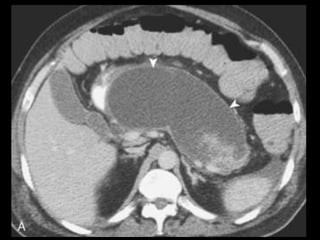

PANCREATITE AGUDA GRAVE

Ocorre em 20-30% dos pacientes com PA;

Caracteriza-se por evolução protraída, insuficiência

de múltiplos órgãos e necrose pancreática;

Necrose pode ser difusa ou esparsa, superficial ou

profunda, e pode afetar qualquer parte do

pâncreas;

A necrose ocorre logo de início, em 24-48 horas,

ela permanece estável, com raras exceções.

Os resultados TC são melhores indicadores

prognósticos que sistemas de escores numéricos,

devido a sua maior sensibilidade e especificidade.

A administração de contraste IV é essencial,

especialmente em pacientes com PA grave, para

visualizar o pâncreas, diferenciar a glândula de

coleções líquidas adjacentes e do tecido

inflamatório peripancreático e demonstrar a

necrose pancreática.

Áreas focais ou difusas de realce diminuídas ou

ausente à TC contrastada dinâmica constituem

áreas de isquemia ou necrose.

TC tem precisão geral de 87% com S e E de 100%

para necrose extensa e 50% com áreas menores.